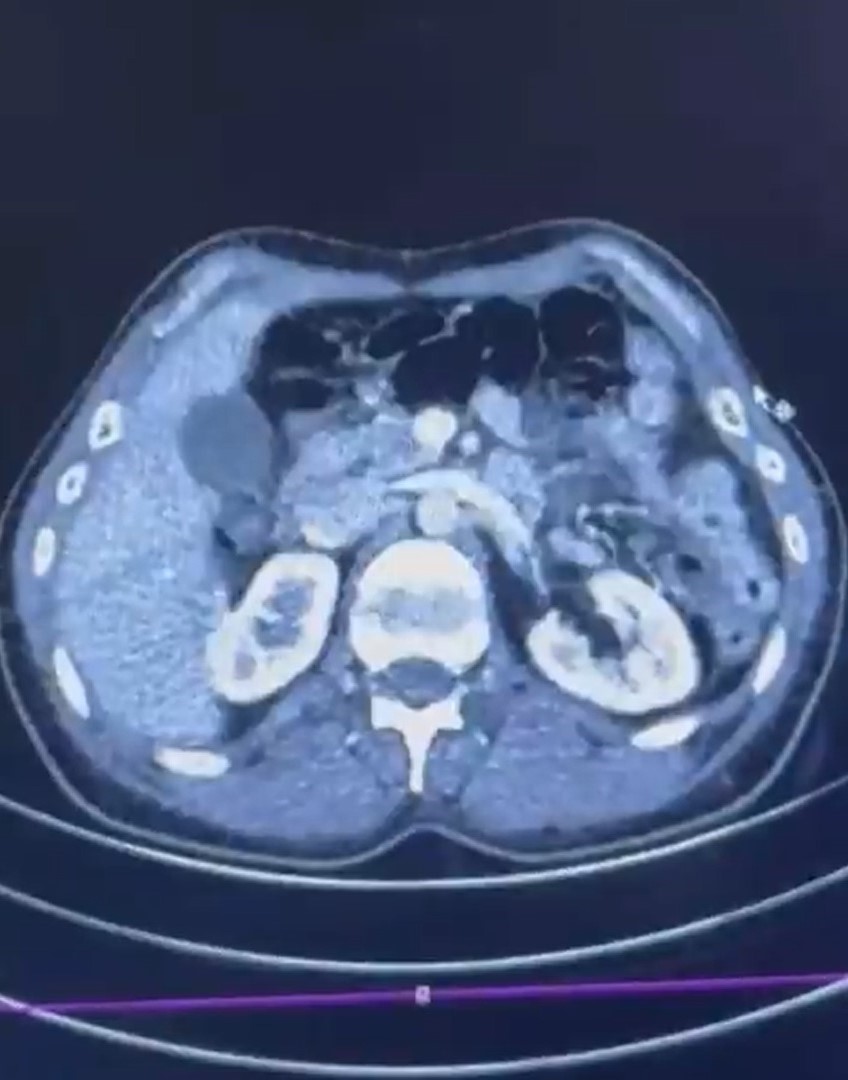

Düzenlenen operasyonda; S.C., R.B.C. ve G.M. yakalandı. S.C. ve R.B.C.'nin Kayseri Şehir Hastanesi'nde yapılan iç beden muayenelerinde, mide kısımlarında bulunduğu tespit edilen 50 adet kapsül şeklinde toplam 554 gram uyuşturucu madde ele geçirildi. Şüpheliler gözaltına alınarak haklarında 'Uyuşturucu Madde Ticareti Yapmak' suçuyla işlem başlatıldı.